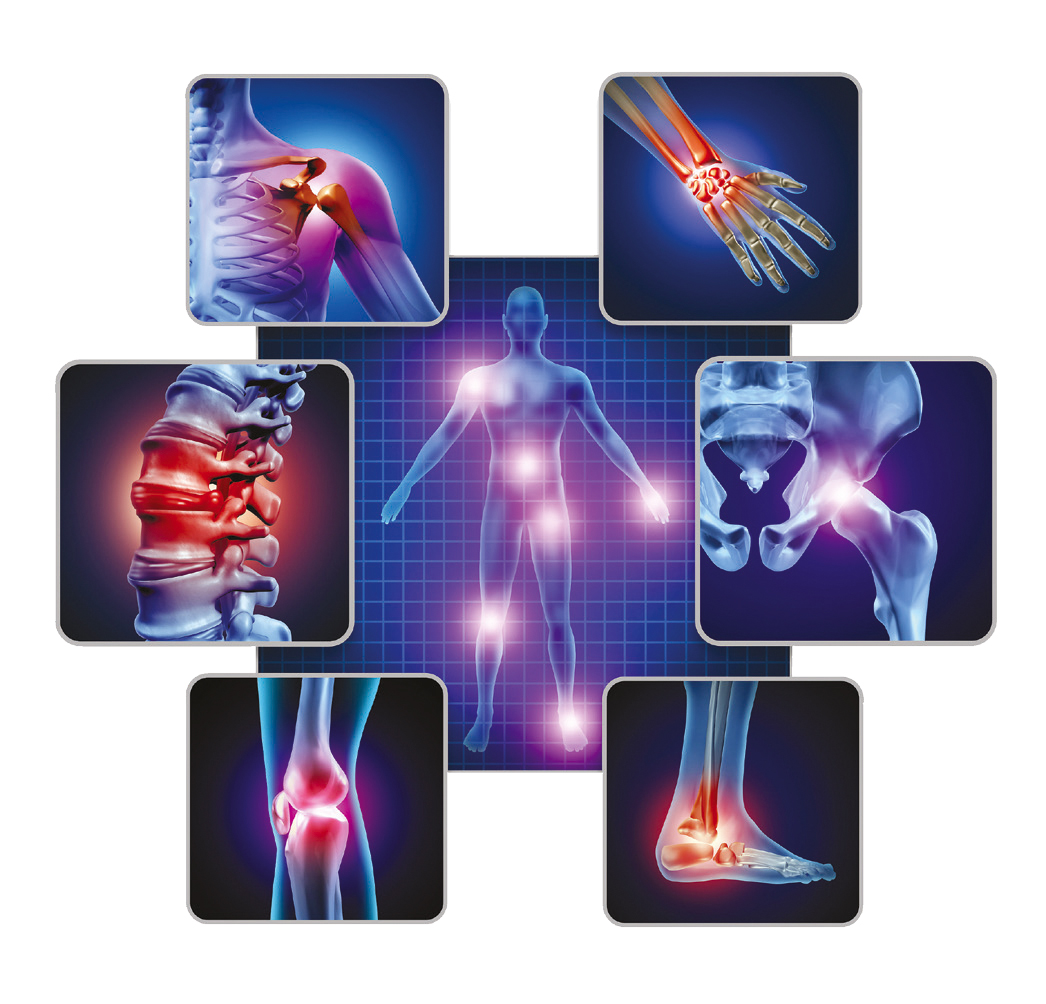

OSTEOARTRİT (OA) NEDİR?

- Osteoartrit (Kireçlenme), en yaygın görülen kronik kıkırdak hastalığı olarak bilinir. Kıkırdak, aşınma ve yıpranma ve/veya mekanik stres sonucu deforme oldukça, hücre dışı matris (ECM) kaybına yol açan şişme, ağrı ve inflamasyona sebep olur.

- Diz osteoartriti, sıklıkla eklem içindeki ve çevresindeki yapıları içeren ve ilerleyen bir eklem hastalığıdır ve eklem kıkırdağı lezyonları, sinovit, subkondral skleroz ve osteofitlerle karakterize bir patoloji olarak kabul edilir.

- Diz osteoartriti çoğunlukla yavaş ilerleyen kıkırdak dejenerasyonu ve inflamasyonu ile karakterize edilen bir eklem hastalığıdır. Diz osteoartriti genellikle diz ağrısına ve hastanın hareketlerinin kısıtlanmasına sebep olur (örn. Yürümek ve merdiven çıkmak).

- OA ağrısı genellikle yapılan aktivite ile alakalıdır. Diz osteoartritinde, merdiven çıkmak, sandalyeden kalkmak ve uzun mesafe yürümek ağrıya sebep olabilir. Sabah tutukluğu genellikle 30 dakikadan kısa sürer. Hastalar genellikle bir dayanıksızlık semptomu olarak dizlerinin “bağının çözüldüğünü” ifade ederler.

OSTEOARTRİT (OA) SEMPTOMLARI NELERDİR?

OA eklem ağrısı tipik olarak aktivite ile şiddetlenen ve dinlenme ile rahatlayan bir hastalık olarak tanımlanır. Daha ilerlemiş olan OA ise dinlenme anında ve geceleri ağrıya neden olabilir ve uykusuzluğunda etkisiyle ağrı daha da şiddetlenebilir.